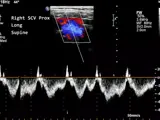

With SIMTICS students can learn and practice a wide range of ultrasound procedures and protocols, anytime and anywhere. No downloads and no special equipment required. Choose from 24+ hours of content featuring a range of ultrasound procedures, including general, cardiac and vascular assessments and several that students may not be allowed to practice during externships. As well as interactive simulations, each module includes a demonstration video, explanatory text with key terms and illustrations, an applied anatomy section with 2D and 3D images, and at least one quiz to test your theory knowledge.